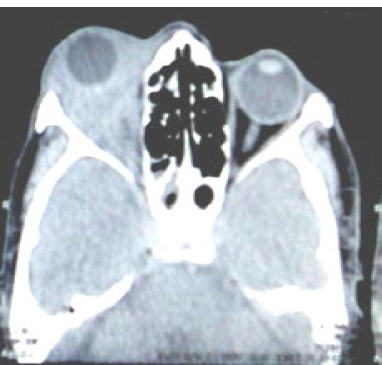

Orbital pseudotumor is nonspecific orbital inflammation (NSOI). It is a benign, non-infectious, space-occupying inflammatory lesion of the orbit. NSOI can affect various tissues in the orbit, such as the lacrimal gland and extraocular muscles. The most common classification is based on clinical presentation. Bacteria, viruses, fungi, or parasites can cause infectious orbital inflammation. It is a diagnosis of exclusion after ruling out inflammatory, infectious, and neoplastic causes. We present a case of a male in his sixties who presented with progressive pain, swelling, blurry vision, and forward protrusion of his right eye. He had no history of trauma or recent illness. His general physical and systemic examination was within normal limits. His ocular examination showed eyelid edema, erythema, eccentric proptosis, and a mature cataract in his right eye. His left eye showed a lenticular opacity. CT orbit revealed a homogenous isodense lesion observed without any globe distortion. A diagnosis of orbital pseudotumor was made. The patient was treated with oral corticosteroids, and an excision biopsy was done, resulting in symptomatic improvement and regression of inflammation at follow-up. In complex cases of inflammatory orbital pseudotumor, particularly those with granulomatous inflammation, some initial success has occurred with monoclonal antibodies against tumor necrosis factor (TNF)-alpha or with lymphocyte depletion using rituximab. Our patient, however, responded well to an excision biopsy and a course of oral steroids.